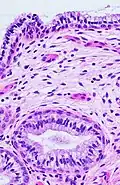

The endocervical mucosa is about 3 mm (0.12 in) thick and lined with a single layer of columnar mucous cells. It contains numerous tubular mucous glands, which empty viscous alkaline mucus into the lumen.[4] In contrast, the ectocervix is covered with nonkeratinized stratified squamous epithelium,[4] which resembles the squamous epithelium lining the vagina.[17]: 41 The junction between these two types of epithelia is called the squamocolumnar junction.[17]: 408–11 Underlying both types of epithelium is a tough layer of collagen.[18] The mucosa of the endocervix is not shed during menstruation. The cervix has more fibrous tissue, including collagen and elastin, than the rest of the uterus.[4]

The squamocolumnar junction of the cervix, with abrupt transition: The ectocervix, with its stratified squamous epithelium, is visible on the left. Simple columnar epithelium, typical of the endocervix, is visible on the right. A layer of connective tissue is visible under both types of epithelium.

In prepubertal girls, the functional squamocolumnar junction is just within the cervical canal.[17]: 411 Upon entering puberty, due to hormonal influence, and during pregnancy, the columnar epithelium extends outward over the ectocervix as the cervix everts.[15]: 106 Hence, this also causes the squamocolumnar junction to move outwards onto the vaginal portion of the cervix, where it is exposed to the acidic vaginal environment.[15]: 106 [17]: 411 The exposed columnar epithelium can undergo physiological metaplasia and change to tougher metaplastic squamous epithelium in days or weeks,[17]: 25 which is very similar to the original squamous epithelium when mature.[17]: 411 The new squamocolumnar junction is therefore internal to the original squamocolumnar junction, and the zone of unstable epithelium between the two junctions is called the transformation zone of the cervix.[17]: 411 Histologically, the transformation zone is generally defined as surface squamous epithelium with surface columnar epithelium or stromal glands/crypts, or both.[20]